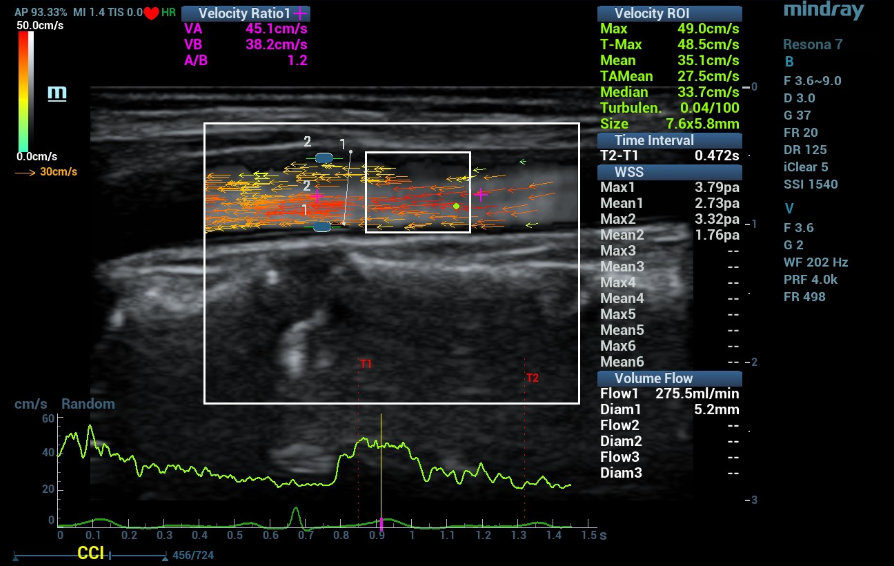

A new Doppler technology based on Vector Flow Imaging (VFI), a representation of flow supported by high frame rate Doppler using multidirectional blocks technology enables the analysis of complex high-speed flow patterns, represented by omnidirectional Doppler flow vectors with proportional color and size. This new development is called V FLOW.

With a wider Region of Interest (ROI) than PW Doppler and more precise vectorial representation than color grading, using V FLOW it is possible to measure velocity and flow gradients at different sections of a vessel, within the same beat, the wall shear stress in different regions of the vessel wall or plaques and the degree of flow turbulence. This advance conducts to a new era of quantitative and qualitative vascular flow evaluation, going into deep of complex flow patterns and the physiopathology of the vessel wall structure and function. This may lead to a better understanding of the evolution of atherosclerotic lesions from their beginning to their complications.

2. US findings: Carotid atherosclerotic plaques in left carotid artery bulb. Evaluations: Complete US investigation of carotid and femoral arteries. Evaluation of Pulse Wave Velocity and endothelial function test using forearm ischemia hyperhemia were performed. Analysis of plaques in left common carotid artery included, plaque area, B Hist plaque composition analysis (Grey Scale Mean GSM), V FLOW parameters speed gradient, flow, WSS and turbulence) and also LCCA were evaluated using V FLOW and RVQS stiffness evaluation (Pulse Wave Velocity (PWV) and Hardness coefficient). (Table 1)

LCCA speed and flow were comparable, but the stiffness was higher in the LCCA of the Stiff plaque (PWV 9,6 vs. 5 m/s and Hardness coefficient 7,6 vs 1,9) compared to soft plaque LCCA. The Stiff plaque showed a smaller area (14 vs 25 mm2), higher GSM (111 vs 73 GS) and lower values of WSS in the proximal shoulder (0,68 vs 1,41 Pa), the tip (0,66 vs 0,94 Pa) and distal shoulder (1,3 vs. 1,64 Pa) than the soft plaque. The pattern of the WSS shows a ŌĆ£depressionŌĆØ in the proximal shoulder of the stiff plaque and in the top center of the soft plaque, probably linked to the expansion of the last one (almost 10% compared with 0% of the stiff plaque, see bulb diameter syst/diast). (Table 1)

Two cases of hypertensive patients are presented with two characteristic plaques in the left carotid artery, one is soft (OM) and the other (SA) is stiff. The hemodynamic behavior using V FLOW (speed gradient, flow, WSS at different points of plaque surface) in each case, were analyzed and compared.

The neighboring artery of the hard plaque was stiffer compared with the soft plaque and the expansion of the first plaque lower. At comparable levels of speed and flow and negligible levels of gradient, the WSS behavior was different in the stiff plaque than in the soft plaque, showing different vulnerable regions in each one. These findings could lead to a better comprehension of the development and evolution of atherosclerotic plaques and eventually follow up the response to treatment (statins or specific CV treatments). (Graphics 1 Stiff Plaque Graphics 2 Soft Plaque)